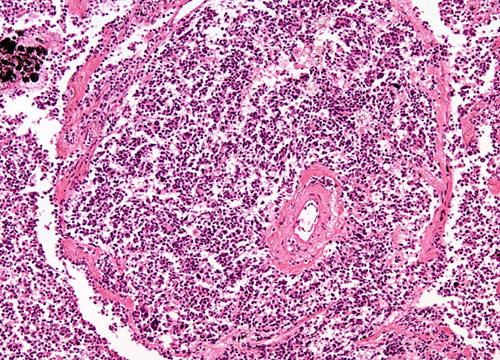

Small cell (oat cell) carcinoma